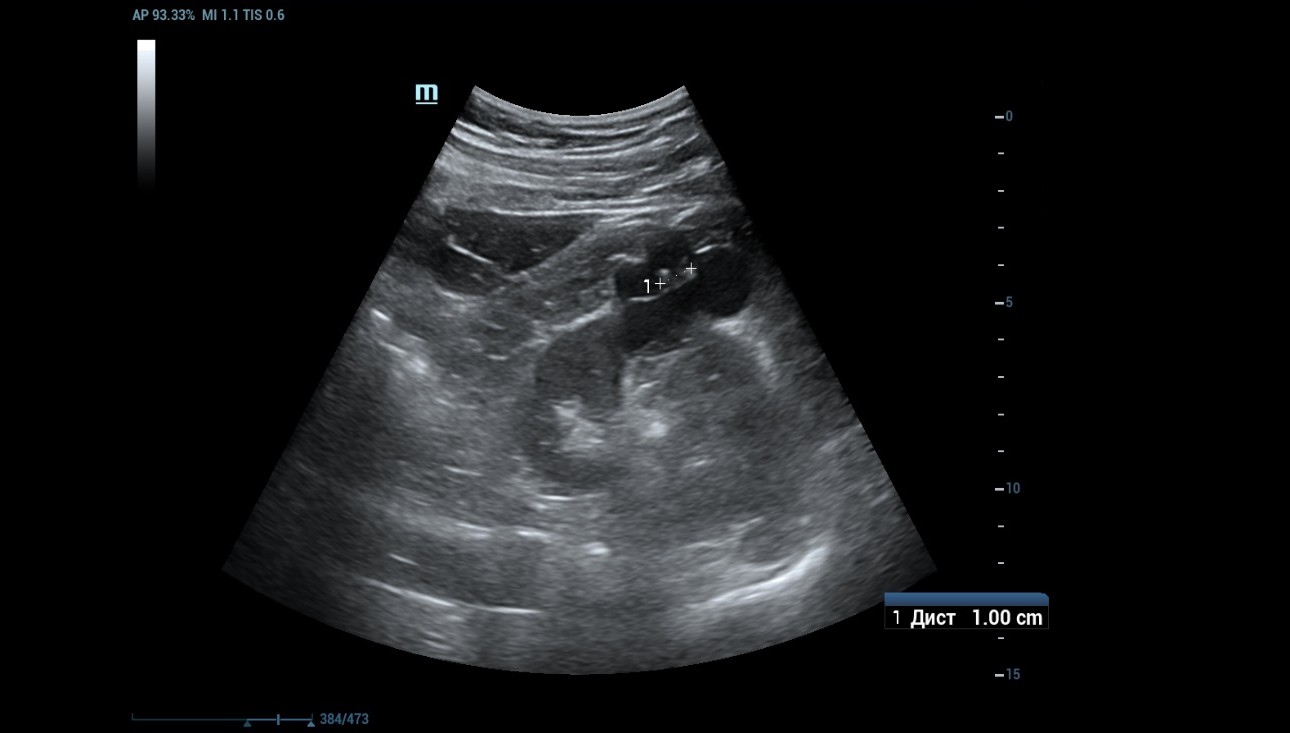

1) B-mode and Power Doppler mode imaging

An ultrasound examination was conducted using a Resona 7 ultrasound machine (Mindray, China) with the SC5-1U transducer. A cystic lesion measuring 46x35 mm in the middle part of the right kidney was found with multiple septa measuring up to 2 mm thick. When scanning the right kidney, a cystic mass with clear, even contours, 46 x 35 mm in size with multiple thick partitions (about 4 partitions) is visualized in the middle part of the cortex. It is homogeneous and anechoic within the cystic mass. A hyperechoic node measuring 10 mm in length was seen protruding into one of the cystic partition (Figure 1 and 2).